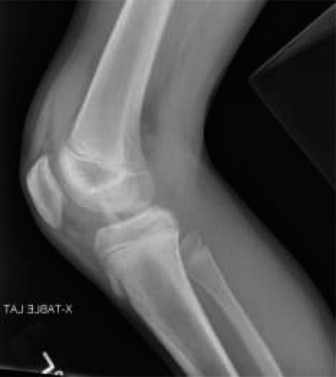

Initial radiographic evaluation in the emergency department included standard non weight bearing anteroposterior, lateral, and oblique views of the left knee.

The anteroposterior radiograph demonstrated a distinct avulsion fracture of the tibial eminence, localizing to the anterior intercondylar area. The primary fracture fragment appeared partially displaced in a lateral and superior direction. The lateral radiograph was paramount in defining the true extent of the pathology. It clearly visualized the anterior displacement and superior hinging of the avulsed fragment, confirming the clinical suspicion of a mechanical block to extension caused by notch impingement.

Careful scrutiny of the radiographs is required to differentiate the primary eminence fragment from other potential osseous avulsions. The lateral view must be evaluated for the presence of a Segond fracture, a small vertically oriented avulsion off the anterolateral proximal tibia, which is highly pathognomonic for an anterior cruciate ligament tear and anterolateral complex disruption. In this case, no Segond fracture was identified. The intercondylar notch view, if obtainable, can provide additional perspective on the medial to lateral dimensions of the fracture bed, though it is often difficult to acquire in the acutely injured, painful knee.